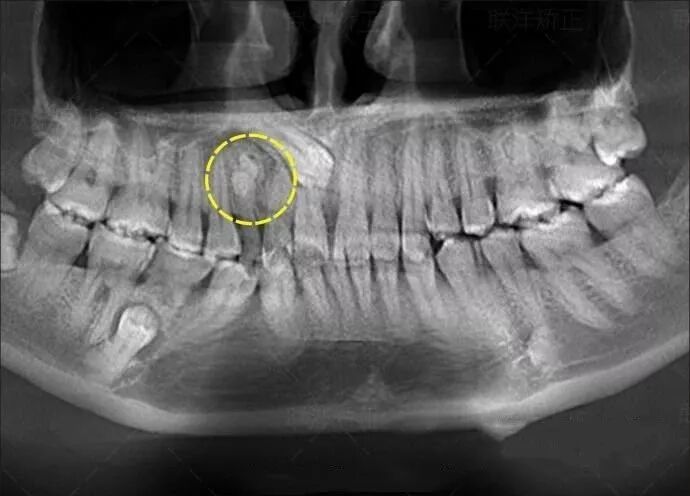

拍一次全口曲面断层

=22微西弗

=22张小牙片

=220根香蕉

等于坐飞机5.4小时

拍一次全口曲面断层=吃220根香蕉

预知其他病变:如颌骨内有无埋伏牙,多生牙,囊肿等。